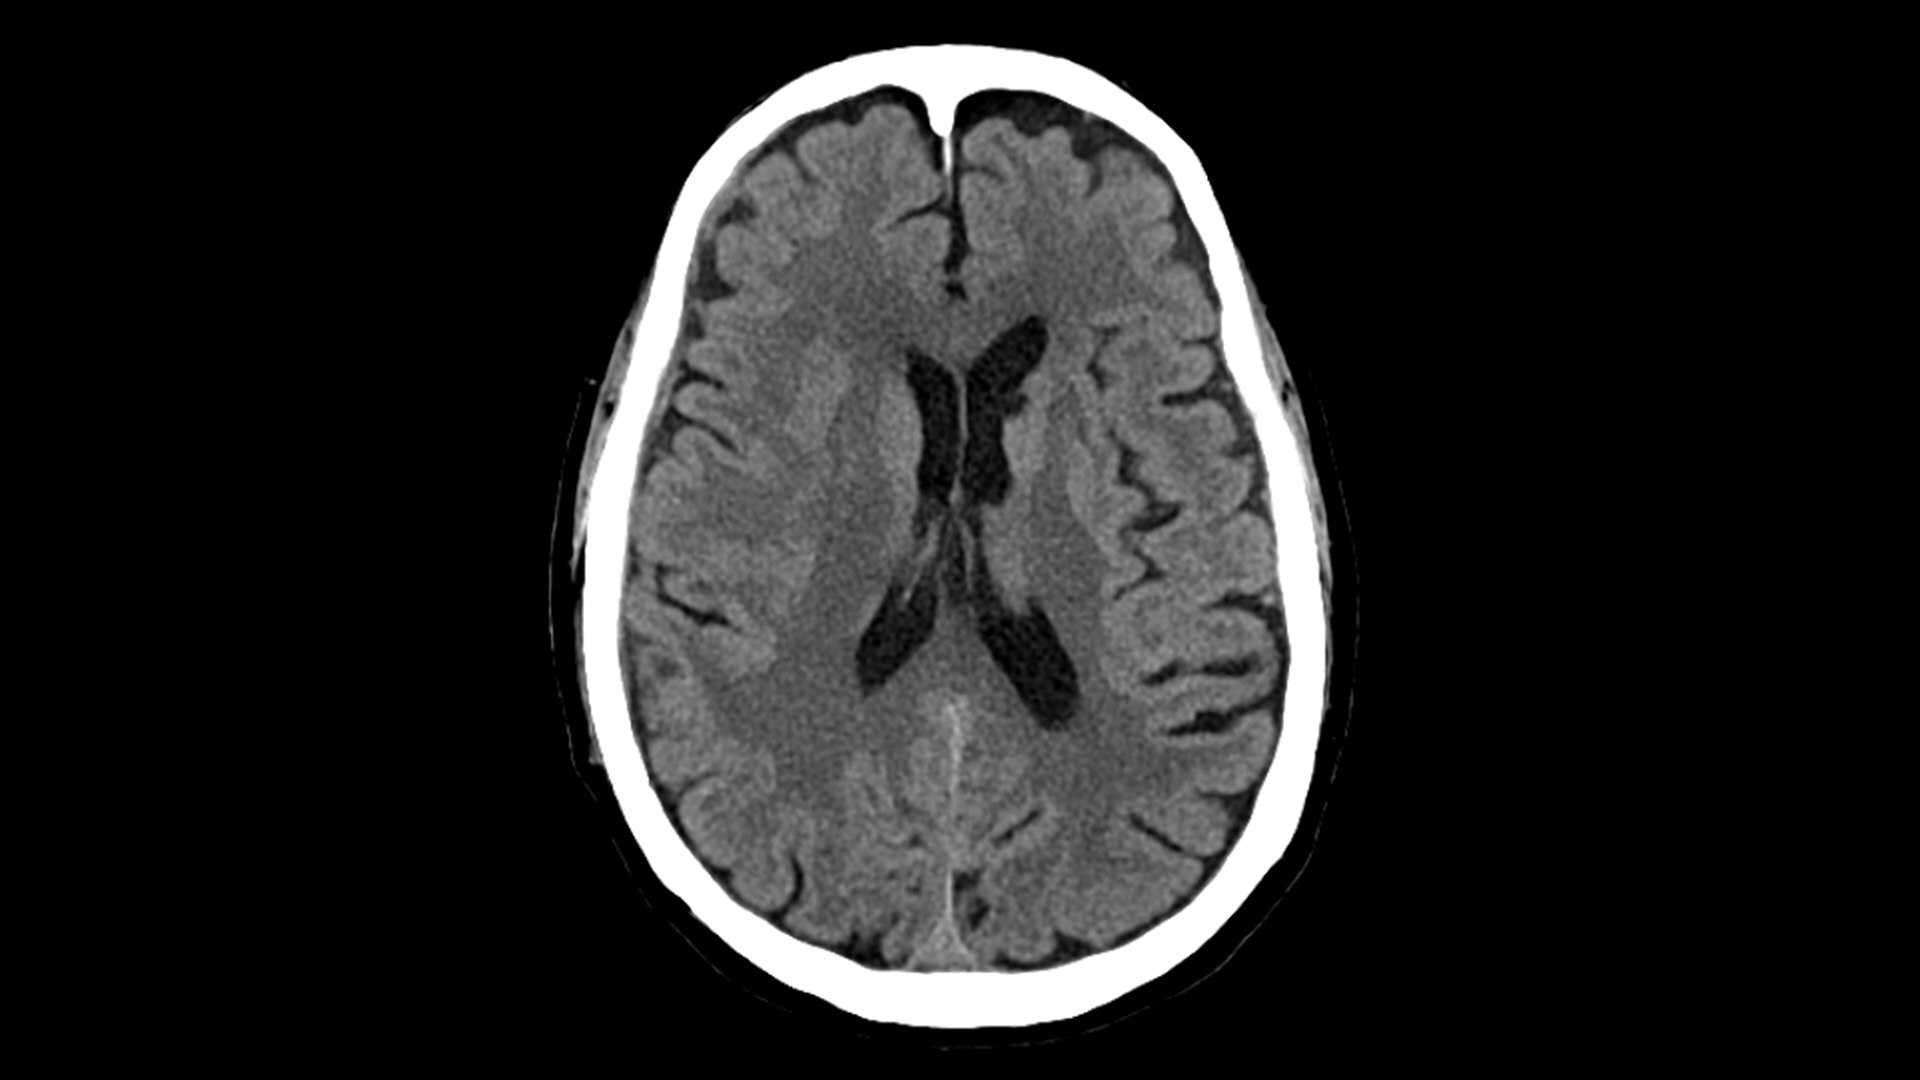

Photonova Spectra provides wide coverage in ultra-high definition imaging with exceptional acquisition speeds, designed to allow you to see your patient’s anatomy in exquisite detail.

With ultra-high spatial resolution scanning capability, Photonova Spectra is designed to help you see incredibly fine details, such as coronary plaque delineation, small microvascular vessels and even tiny structures of the inner ear.

Experience our industry-leading 8 cm detector coverage, combined with up to 0.23 sec rotation speed and ultra-high sampling rates featuring a 50 cm field of view (FOV) in all scan modes. This enables wide-coverage ultra-high definition imaging with reduced organ movement for exceptional image clarity.